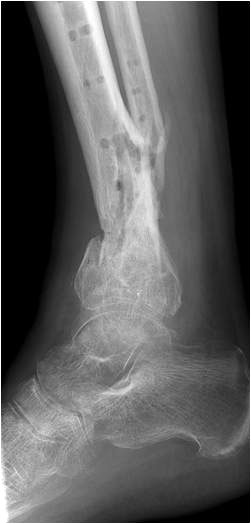

• Revision einer gescheiterten Fusion des OSG/ USG (Abbildung 3, Abbildung 4).